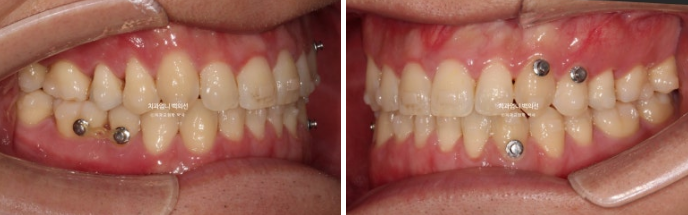

교합과 중심선 개선, 소구치 회전 등을 위해서 추가제작에 들어갔고 24년 8월부터 11월까지 4달간 추가장치를 꼈습니다.

24.11

어금니 교합은 안정적으로 좋아졌지만 아주 약간의 중심선 불잏치가 남아 재제작 한 세트 더 했습니다.